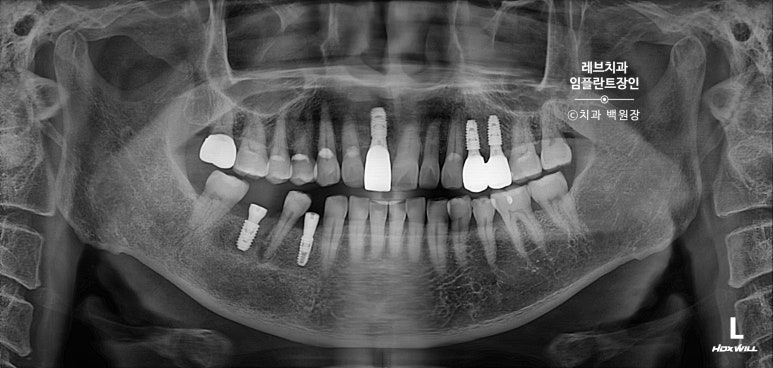

치과용 파노라마 사진을 보시면, 아주 짧은 뿌리만이 남아있는 것을 보실 수 있어요..

고개를 돌려서 보면, 뿌리만 있는 치아들이 몇개 보이고...

치아 목부위 (치경부)에 충치가 있는 치아들도 여러개 보여요.

파노라마 엑스레이 사진에서도 알맞게 제작된 임플란트 크라운을 보실 수 있을꺼에요.

치과용 파노라마 사진에서도 왼쪽 위 송곳니 주변으로 잇몸뼈가 사라진 것을 보실 수 있는데요,

확대해볼 수 있는 치근단 방사선 사진을 보시면, 송곳니 뿌리 주변으로 거무딩딩하게 뼈가 없어진 것을 보실 수 있습니다.

완성 후 촬영한 치과용 방사선 엑스레이 사진에서도, 깔끔하게 완성된 보철물을 보실 수 있을겁니다.